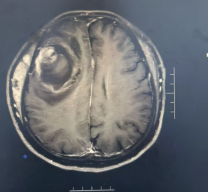

到院行头CT、MRI检查后初步诊断为颅内占位性病变,但因其影像学表现非常复杂,不同于常见颅内肿瘤,吴镝主任所带领的治疗团队联合北京天坛医院等的数位专家对此病例进行充分的分析讨论,肿瘤性质考虑为颅内黑色素瘤,肿瘤位于重要功能区、边界不清晰、血运极其丰富,手术难度很大,最终通过充分论证制订了通过精准入路、显微精细操作、术中严密监测等预案,力争把手术风险降到最低,为后续综合治疗创造条件。

术前